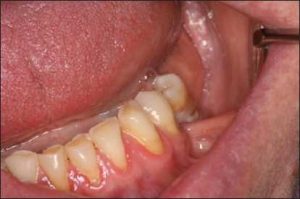

The loss of a single tooth or a group of teeth may lead to malposition of the remaining teeth due to their extrusion or tipping (Figure 10-4).

In most cases, the alveolar bone moves occlusally along with the extruded tooth (Figure 10-5). Although not always a practical solution, orthodontic treatment may be beneficial in managing occlusal discrepancies. Another treatment option is the surgical correction of the position of the tooth and the supporting alveolar bone.